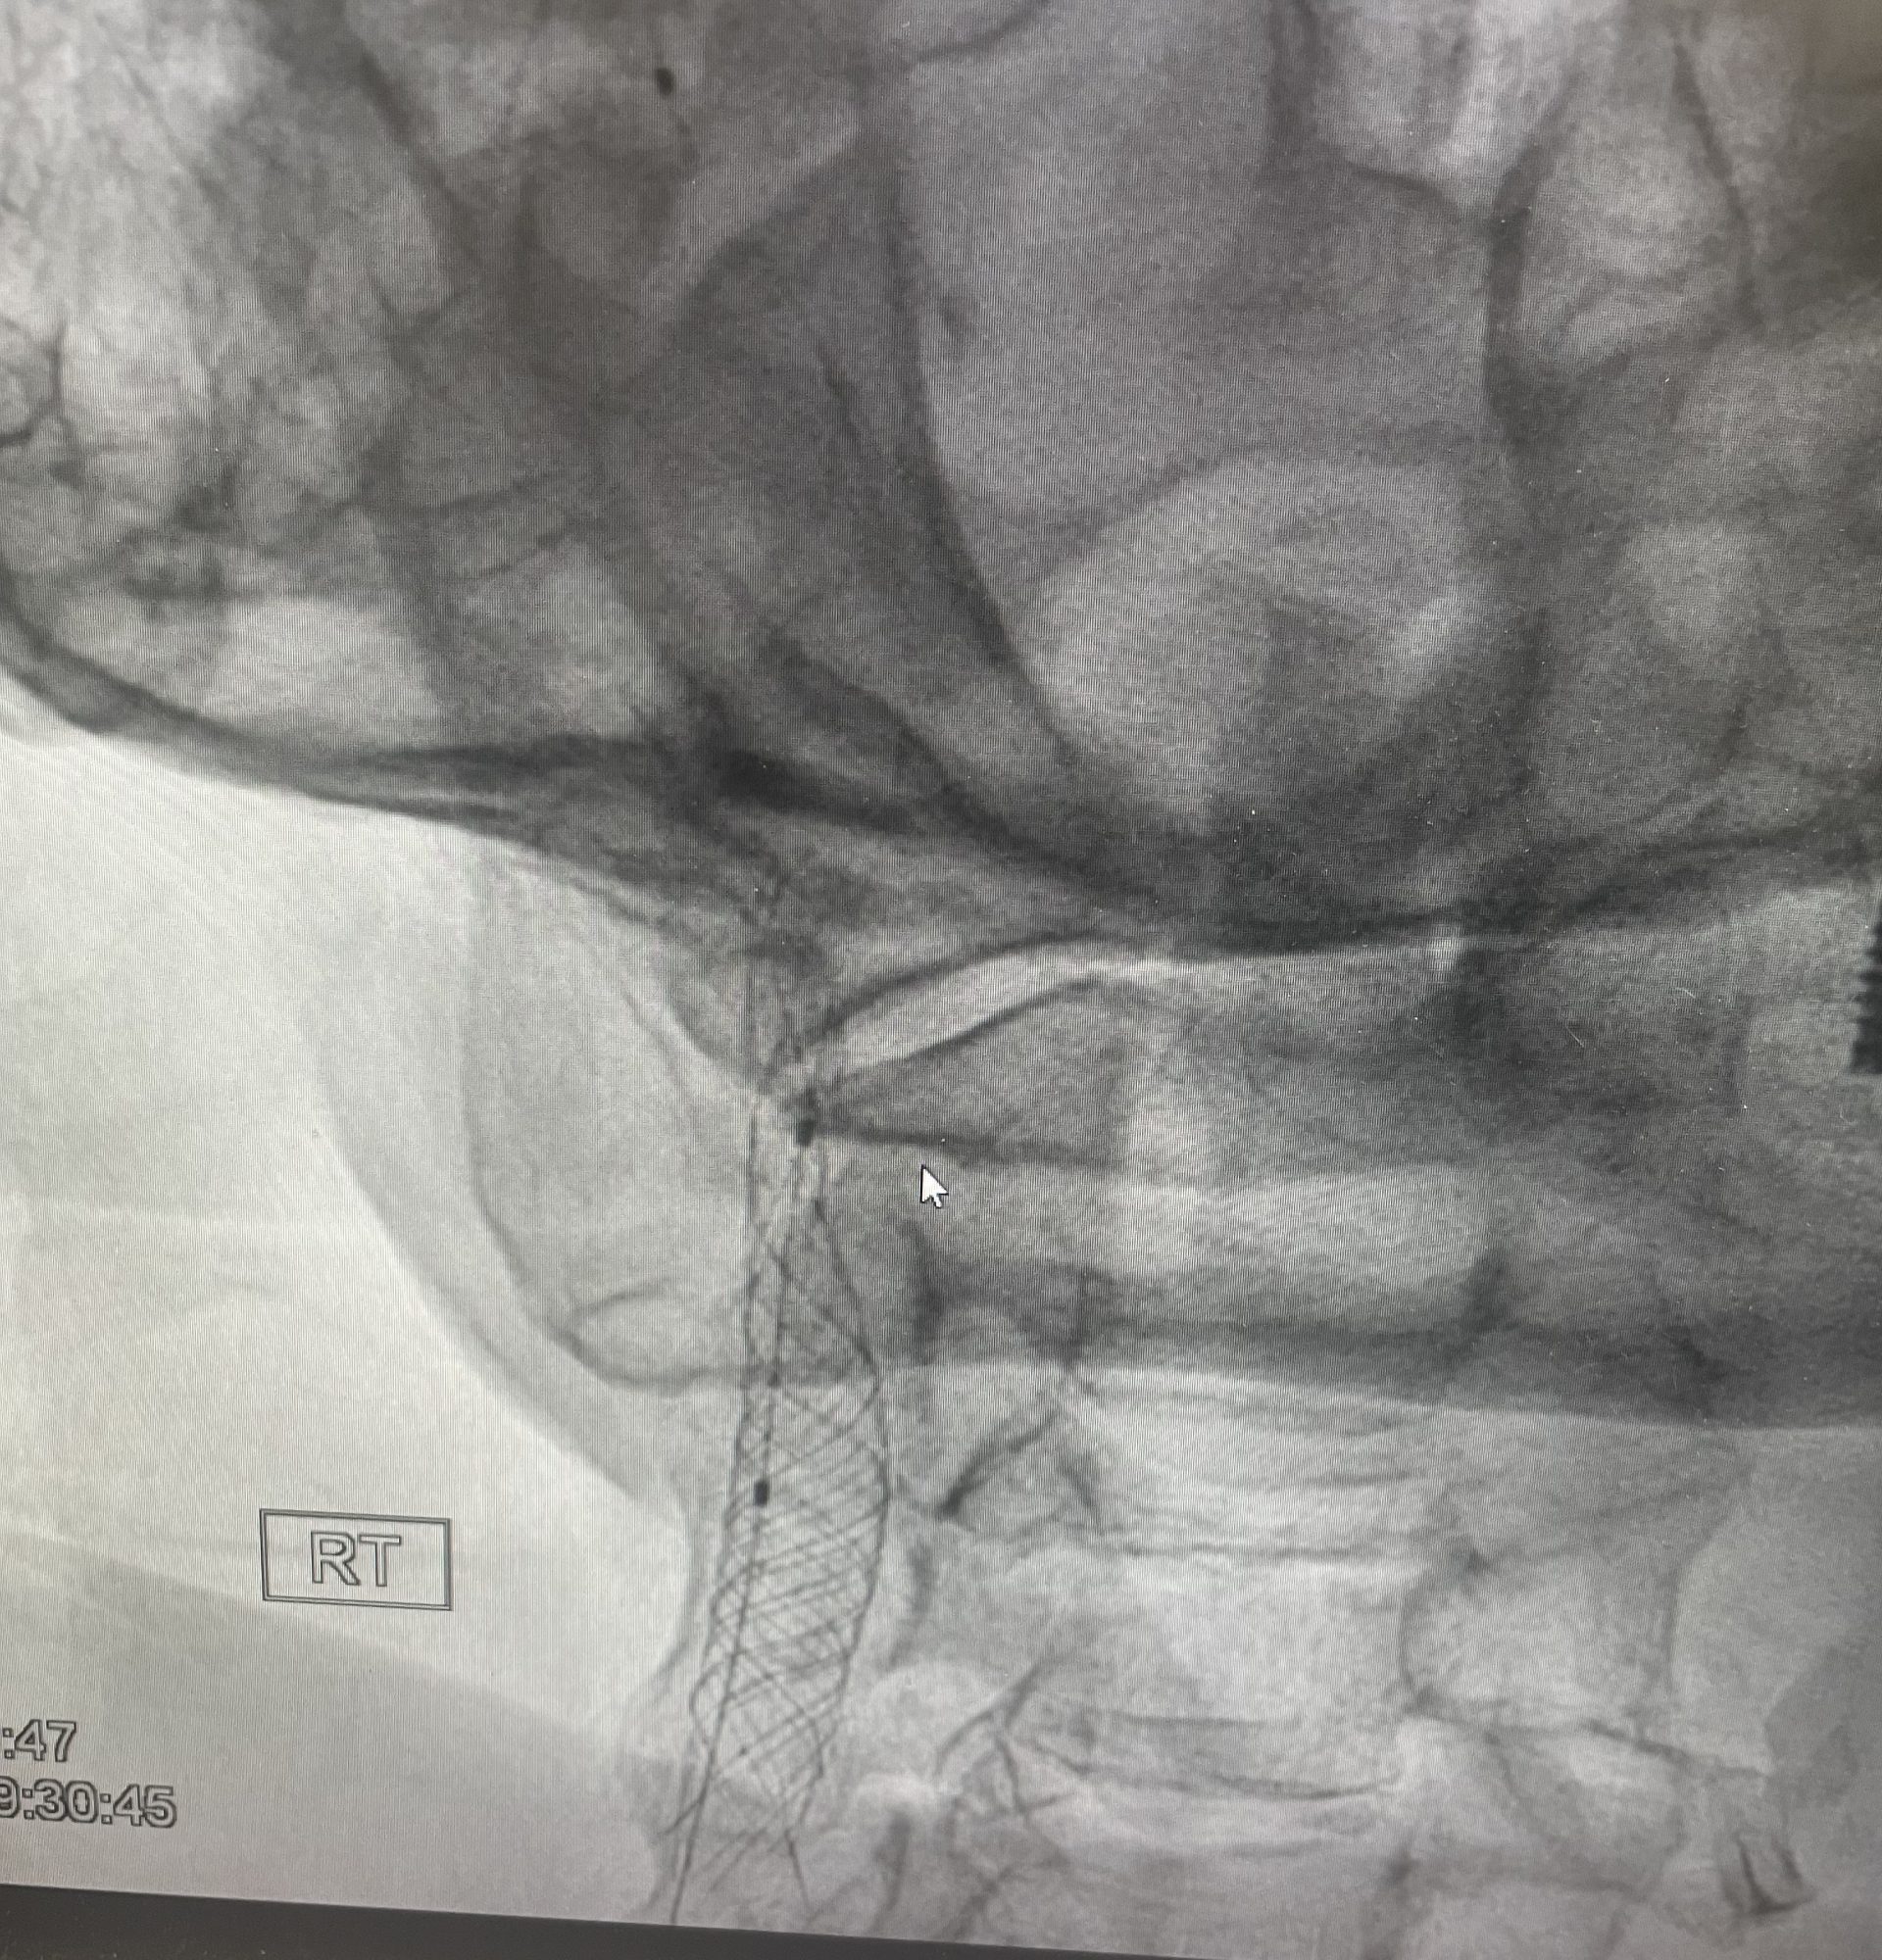

היצרות משמעותית של עורקי הצוואר, אפילו כשהיא “שקטה” לחלוטין (ללא סימפטומים), מהווה גורם סיכון מרכזי לשבץ מוחי איסכמי. ניתוח כלי דם (אנדארטרקטומיה) הוא טיפול יעיל ובטוח, שנחשב במשך שנים רבות לסטנדרט המקובל במטופלים מתאימים, ובמיוחד כאשר יש תסמינים. אולם במסגרת CREST-2 , מחקר שבחן במיוחד מטופלים ללא תסמינים ותוך כדי איזון רפואי מיטבי — נראה כי הניתוח לא סיפק תוספת הגנה מעבר לטיפול שמרני בלבד. לעומת זאת, בחולים דומים, צינתור ופתיחה של ההיצרות עם סטנט, תוך שימוש בפילטר המגן מתסחיפים – הציג יתרון ברור וחד משמעי , בהשוואה לטיפול תרופתי מיטבי, ובניגוד לניתוח כלי הדם.

אכן -ההמלצה על יעילות מוגברת של צינתור עורקי הצוואר, קרוטיד, מחייבת הפניה למרכז צנתורים מומחה בעל ניסיון, העושה שימוש רוטיני בפילטר להגנה מפני תסחיף והמסוגל לבצע את פעולה בשיעור סיבוכים נמוך במיוחד.